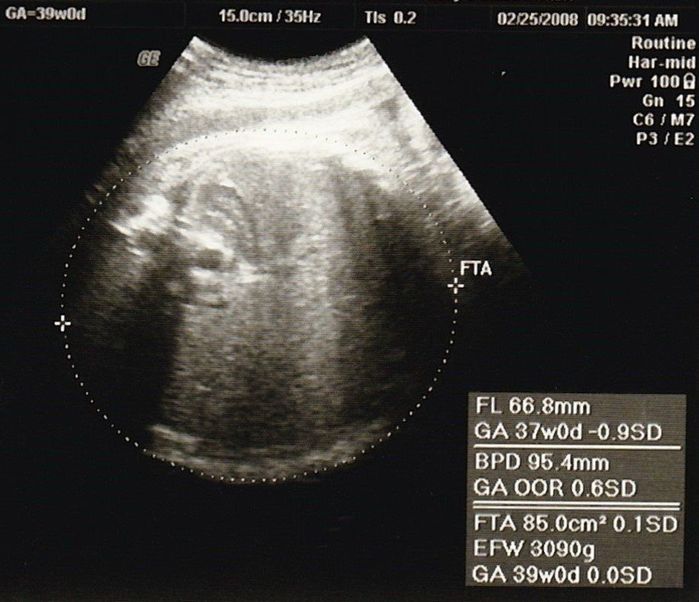

妊娠39週目のエコー写真

母や義母から「まだ生まれないの?」という電話と、たまたま出産予定日が日曜日で、夫、実父、義父も仕事が休み。その日に産まなきゃという義務感が生まれてきました。前日に自宅近くの坂道を上り下り、たっぷり散歩し、スクワットをした結果、無事、予定日当日に出産できました。

妊娠40週0日。予定日に7時間半の陣痛を経て生まれた赤ちゃんは、身長51cm、体重3568g。手足があるか、障害がないかなどが最初に頭に浮かび、元気な男の子が生まれたと分かった瞬間、「やっと終わったー!」いう嬉しさがこみ上げてきました。新生児室の中で一番ビッグで貫禄のある息子を見ると、自分の中からこんな赤ちゃんが出てきたのか、と変な感覚でしたが、毎日見ているうちにどんどん愛着が湧いてきました。赤ちゃんを産んだらというより、育てながらママになり、親子になっていくのだなと実感しました。私はたまたま何の問題もなく、出産まで順調でしたが、それでもとても大変でした。世の中のお母さんはすごい!